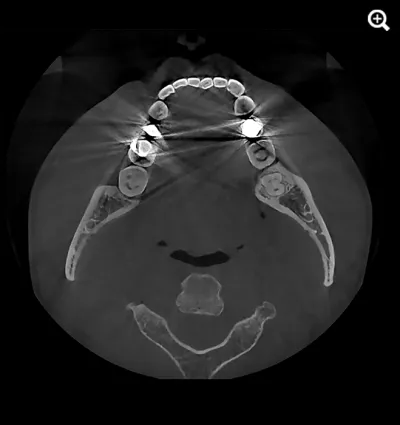

When capturing a CBCT scan, the presence of metal in the oral cavity can introduce artifacts, shadows, and bright streaks that significantly compromise image quality. These distortions may obscure critical anatomical structures, making it more difficult to evaluate bone integrity and surrounding areas—adding complexity to diagnosis and increasing clinical stress.

HDX WILL’s cutting-edge technology now offers a powerful solution through PrecisionMAR™, a metal artifact reduction feature that enhances clarity and ensures more precise imaging—even around metal. This is especially valuable for both dental professionals and ENT specialists focused on comprehensive treatment planning, including airway-focused care.

Minimizes scatter for cleaner imaging

Reduces shading and streak-related artifacts

Clearly defines bone and dental structures adjacent to metal

With improved image fidelity, practitioners can more confidently diagnose conditions, plan treatments, and support airway health initiatives critical to both dental and ENT fields.